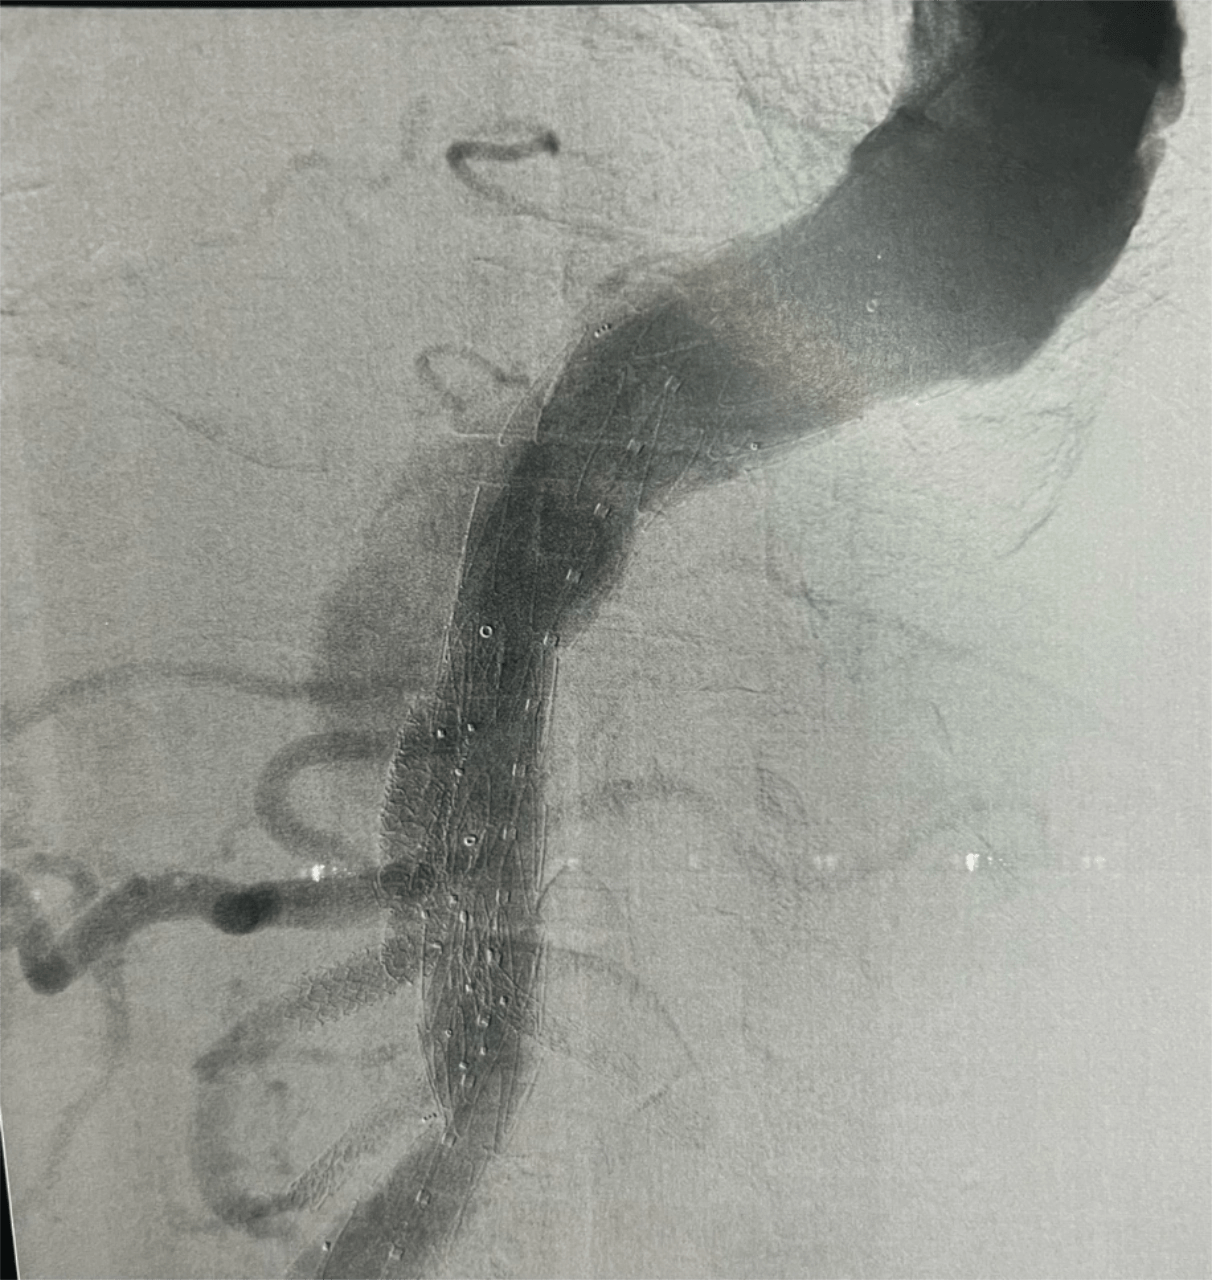

The procedure involved deployment of a custom-made E-xtra Design Multi-branch (EDM) stent graft, with meticulous cannulation and sequential stenting of the visceral arteries via the left brachial approach, including the right renal, left renal, superior mesenteric, and celiac arteries. The iliac limbs were subsequently deployed and optimized with post-dilation.

This complex intervention was performed as part of a staged repair strategy, with the second stage — Thoracic Endovascular Aortic Repair (TEVAR) completed on September 18, 2025 using the Medtronic Valiant system. The staged approach was carefully planned to reduce the risk of spinal cord ischemia during treatment of the extensive thoracoabdominal aneurysm.

Notably, the successful completion of this complex repair required the integration of endovascular technologies from two different device platforms, combining the Artivion E-xtra Design Multi-branch (EDM) stent graft for visceral branch preservation and the Medtronic Valiant thoracic stent graft system for the staged thoracic repair—demonstrating the importance of cross-platform innovation and collaboration to achieve optimal patient outcomes.